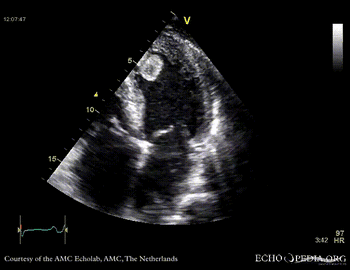

Thrombus in the left ventricle

J. Vleugels, AMC, The Netherlands